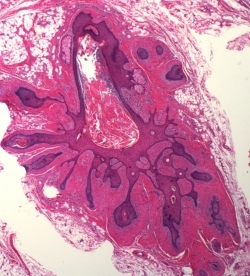

What is this neoplasm?

Trichoadenoma

Trichoadenoma: A nodule on the face or butt that is slightly depressed. Typically confined to the upper dermis and composed of multiple milia or infundibular-like cysts that have a squamous epithelial lining associated with a granular layer and central flakey keratin in the lumen. The stroma can be sclerotic. The lesion is composed primary of cysts with a few thin strands of basaloid cells; if basaloid strands predominate with only a few cysts then lesion is a trichoepithelioma.

John Lennon Glasses